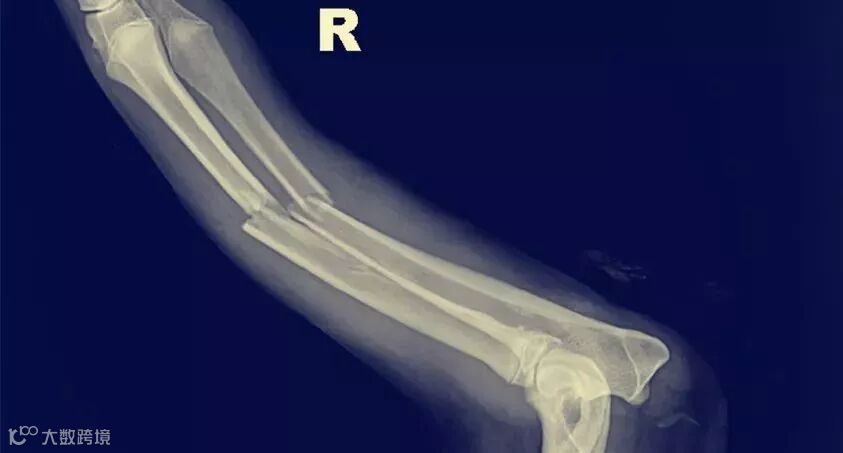

所有骨折均为低冲击骨折,并且可能与骨质疏松症有关。 超过四分之三的病例(79%)仅发生一次骨折,14%发生两次骨折,4%发生三次骨折,2%发生四次骨折。 最常见的骨折部位是椎骨,髋部和腕部。